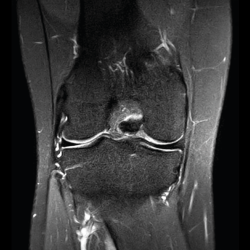

Resonancia magnética

Se basa en la propiedad que poseen los núcleos de hidrógeno de absorber energía electromagnética cuando están sometidos a un campo magnético intenso. La RM representa un mapa de la densidad de protones, o sea, de la distribución de agua por el organismo(12).

Se consiguen unas imágenes de alta resolución para la valoración de meniscos, ligamentos y tendones. Además, es especialmente útil en las rodillas operadas, lesiones tumorales, evaluación del cartílago y la visualización de los nervios(13).

1. Estudio de las estructuras intraarticulares

Es la prueba no invasiva de elección para valorar las lesiones internas de la rodilla(2). Aunque el estudio por RM es a menudo considerado como la prueba diagnóstica de elección para la detección de alteraciones meniscales, se asocia en ocasiones con errores diagnósticos(16).

1.1. Meniscos

Se identifican como estructuras hipointensas en todas las secuencias, con asta anterior y posterior de morfología triangular.

La RM es la técnica de elección en el diagnóstico de la patología meniscal(17)(Figuras 30, 31, 32, 33, 34 y 35).